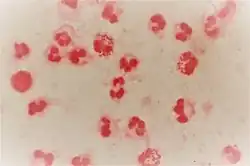

Diagnosis

Traditionally, gonorrhea was diagnosed with Gram stain and culture; however, newer polymerase chain reaction (PCR)-based testing methods are becoming more common.[20][35] If initial treatment fails, a culture should be done to determine the sensitivity of the bacteria to antibiotics.[36]

Tests that use PCR (aka nucleic acid amplification) to identify genes unique to N. gonorrhoeae are recommended for screening and diagnosis of gonorrhea infection. These PCR-based tests require a sample of urine, urethral swabs, or cervical/vaginal swabs. Culture (growing colonies of bacteria in order to isolate and identify them) and Gram-stain (staining of bacterial cell walls to reveal morphology) can also be used to detect the presence of N. gonorrhoeae in all specimen types except urine.[37][38] Studies of the swab sample method for gonorrhea infections have not shown any difference in the number of patients treated, whether the sample was collected at home or in the clinic. The implications for number of patients cured, reinfection rates, partner management, and safety are unknown.[39]

If Gram-negative, oxidase-positive diplococci are visualized on direct Gram stain of urethral pus (male genital infection), no further testing is needed to establish the diagnosis of gonorrhea infection.[40][41] However, direct Gram stain of cervical swabs is not useful because the N. gonorrhoeae organisms are less concentrated in these samples. The chance of a false positive test is also higher for a cervical swab, as Gram-negative diplococci native to the normal vaginal flora cannot be distinguished from N. gonorrhoeae in that context. Thus, cervical swabs must be cultured under the conditions described above. If oxidase positive, Gram-negative diplococci are isolated from a culture of a cervical/vaginal swab specimen, then the diagnosis is made. Culture is especially useful for diagnosis of infections of the throat, rectum, eyes, blood, or joints—areas where PCR-based tests are not well established in all labs.[41][42] Culture is also useful for antimicrobial sensitivity testing, analyzing treatment failure, and epidemiological purposes (outbreaks, surveillance).[41]